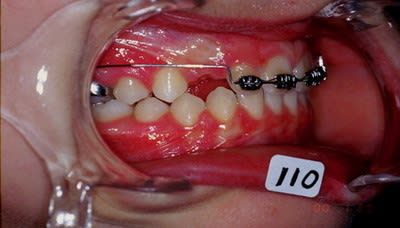

cas n 2

classe II 1 avec pouce

QH + Ecran cuccal pendant 4 mois seulement separent les photos

can 2 suite arc de base pour parfaire le torque des incisives puis surveillance. Aucune mecanique de classe II